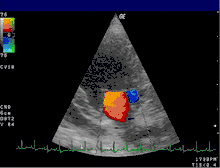

اکوکاردیوگرافی دوپلر

اکوکاردیوگرافی دوپلر روشی است که در آن قلب انسان توسط امواج فراصوت مورد معاینه قرار می گیرد. یک اکوکاردیوگرام از امواج صوتی با فرکانس بالا استفاده میکند تا تصویری از قلب را به نمایش در آورد. در این روش استفاده از فناوری دوپلر نیز جریان و مسیر خون را با استفاده از فناوری اثر دوپلر مشخص می کند.